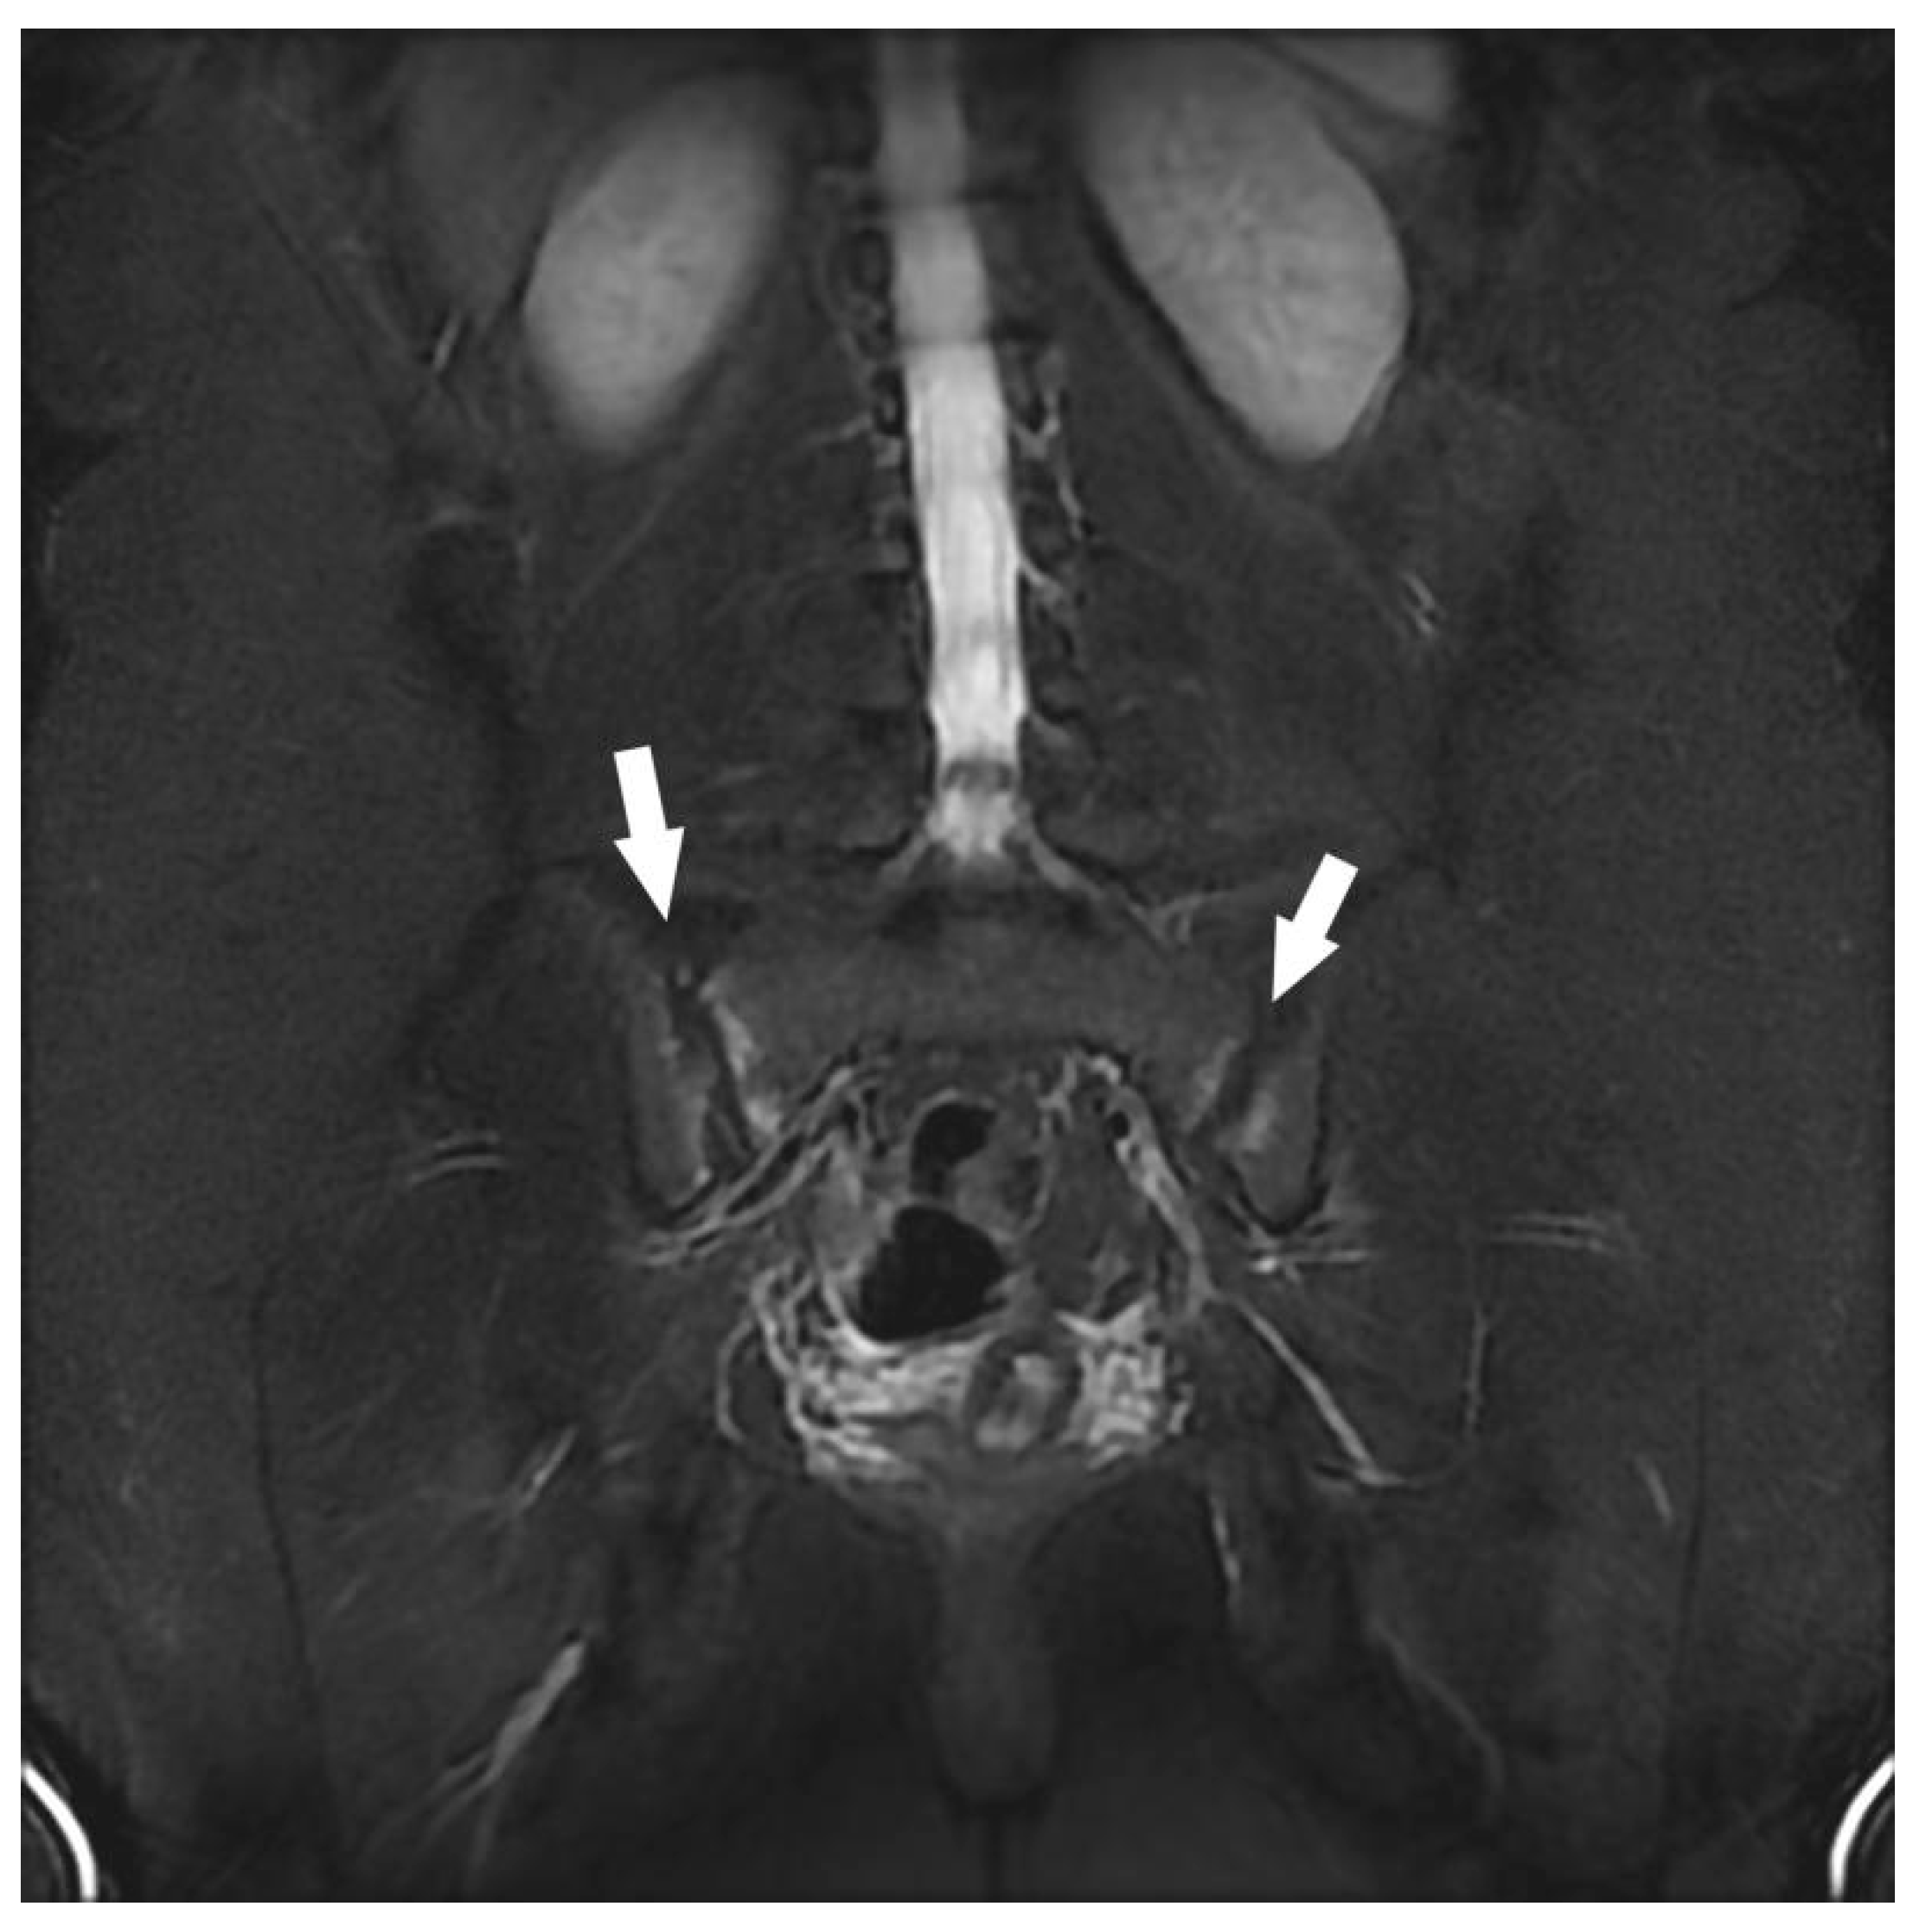

| Sacroiliac Joint | Congestive degenerative arthropathy | 10 |

| Inflammatory sacroiliitis | 4 | |

| Congestive degenerative sacroiliac arthropathy 2 | 8 | |

| Atypical bone lesion (iliac wing, femoral neck, sacrum) 1 | 3 | |